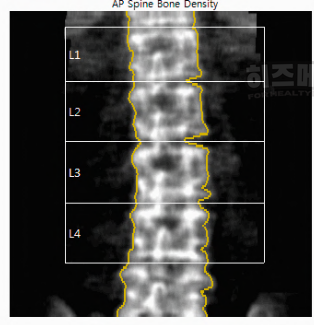

골다공증 수치보는법의 첫 번째 단계는 골밀도 검사입니다. 골다공증 검사는 골밀도 검사(DXA)라는 장비를 사용해 뼈의 밀도를 측정합니다. 뼈 밀도는 뼈가 얼마나 단단한지를 보여주는 수치로, 뼈가 단단하지 않을수록 쉽게 부러질 수 있습니다. 검사 과정은 짧고 간단하며, 방사선 노출이 아주 적어 인체에 안전합니다.

검사 대상 부위로는 주로 허리뼈와 고관절을 측정합니다. 허리뼈는 L1에서 L4까지의 네 개의 요추를 중심으로 검사하며, 이곳은 체중을 많이 받는 부위라서 뼈 상태를 잘 보여줍니다. 고관절은 대퇴골 경부와 대퇴골 전체를 측정합니다. 고관절은 체중의 대부분을 받는 부위로, 나이가 들수록 약해지기 쉽기 때문에 뼈 밀도를 측정할 때 매우 중요한 부위입니다.

1) 요추(L1-L4)

허리뼈 중에서 L1부터 L4까지의 네 개 요추가 골다공증 검사에 사용됩니다. 이 네 개의 요추는 서로 연결되어 있고, 체중을 많이 받기 때문에 뼈 밀도를 확인하기에 좋은 부위입니다.

그런데 L5는 보통 검사에서 제외합니다. L5는 골반에 가까워 다른 요추와 다르게 구조적으로 영향을 받아 결과에 차이가 있을 수 있기 때문입니다. 검사 결과의 일관성을 위해 L1-L4만 사용하는 것이 일반적입니다.